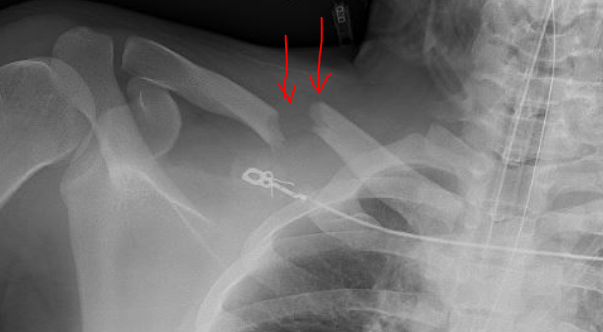

겉으로 보이는 소견으로는 위 사진의 빨간 화살표처럼 쇄골 중심 부위가 솟아오르거나 붓는 증상이 많습니다.

진단에서 가장 중요한 것은 x-ray 방사선 사진입니다.

x-ray상에서는 다음과 같은 모습을 보이게 됩니다

골절이 된 모습을 확인할 수 있고, 얼마나 벌어졌는지, 분쇄(뼈가 으스러짐)은 있는지 등을 확인할 수 있습니다.